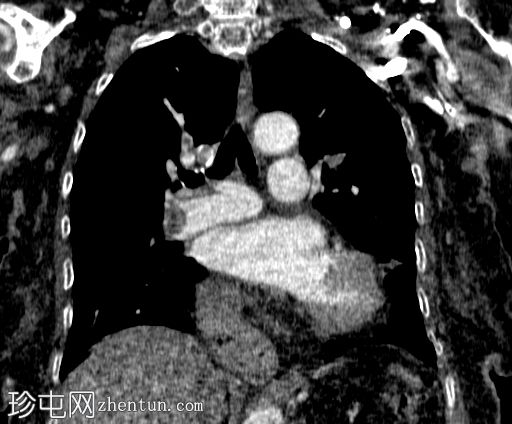

定位像

定位像显示:

心脏轮廓增大

心后梭形不透光影,内含气泡

胃泡缺失,位于正常解剖位置

左上腹结肠内有气体